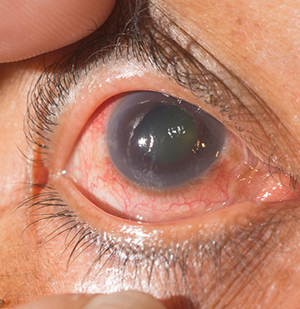

Dr. Tekchandani specializes in a wide range of eye conditions including retinal and vitreous diseases, diabetic retinopathy, macular degeneration, retinal detachment, cataract, glaucoma, refractive errors, and retinopathy of prematurity. He also has expertise in ocular oncology and neuro-ophthalmology.

Vitreoretinal surgery is a highly specialized field of ophthalmology dealing with diseases of the retina and vitreous — the innermost structures of the eye responsible for vision. Dr. Tekchandani performs advanced procedures such as pars plana vitrectomy, scleral buckling, and macular hole surgery to restore and preserve sight.